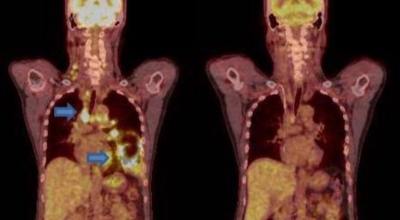

폐암 검사는 X-ray를 통해서 검사하는데 , 크기가 작거나 구석에 위치한 경우 확인이 어려운 경우도 있답니다. 그리고 조직 검사를 통해서 정확한 진단을 하게 되어요. 폐암이 발견되면 종양의 크기나 전이 여부 , 위치에 따라서 수술 여부를 결정하게 되어요.